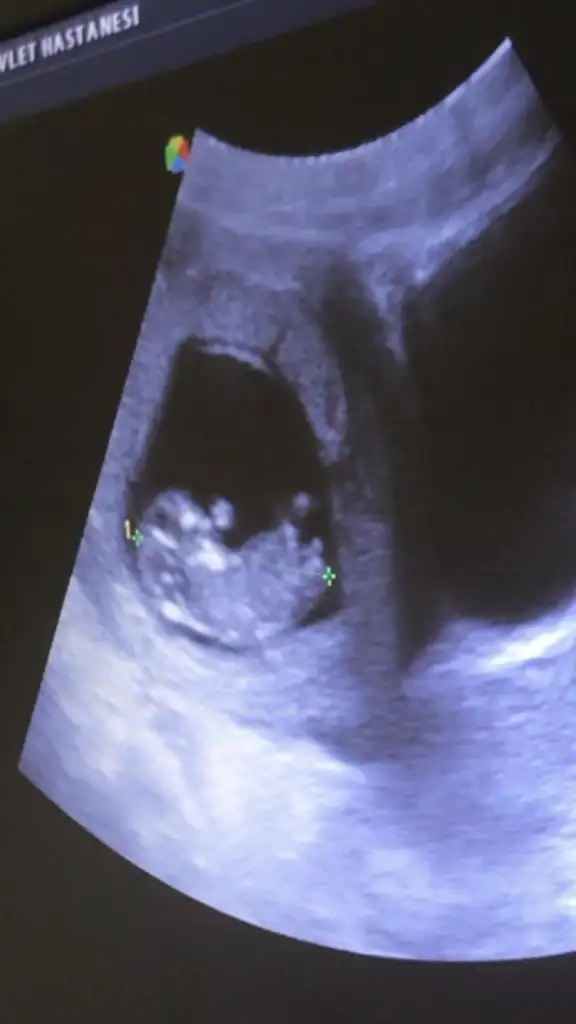

Benim için de tahmin yürütür müsünüz?

• IMG_20210220_141757.webp

IMG_20210220_141757.webp

20,4 KB · Görüntüleme: 159